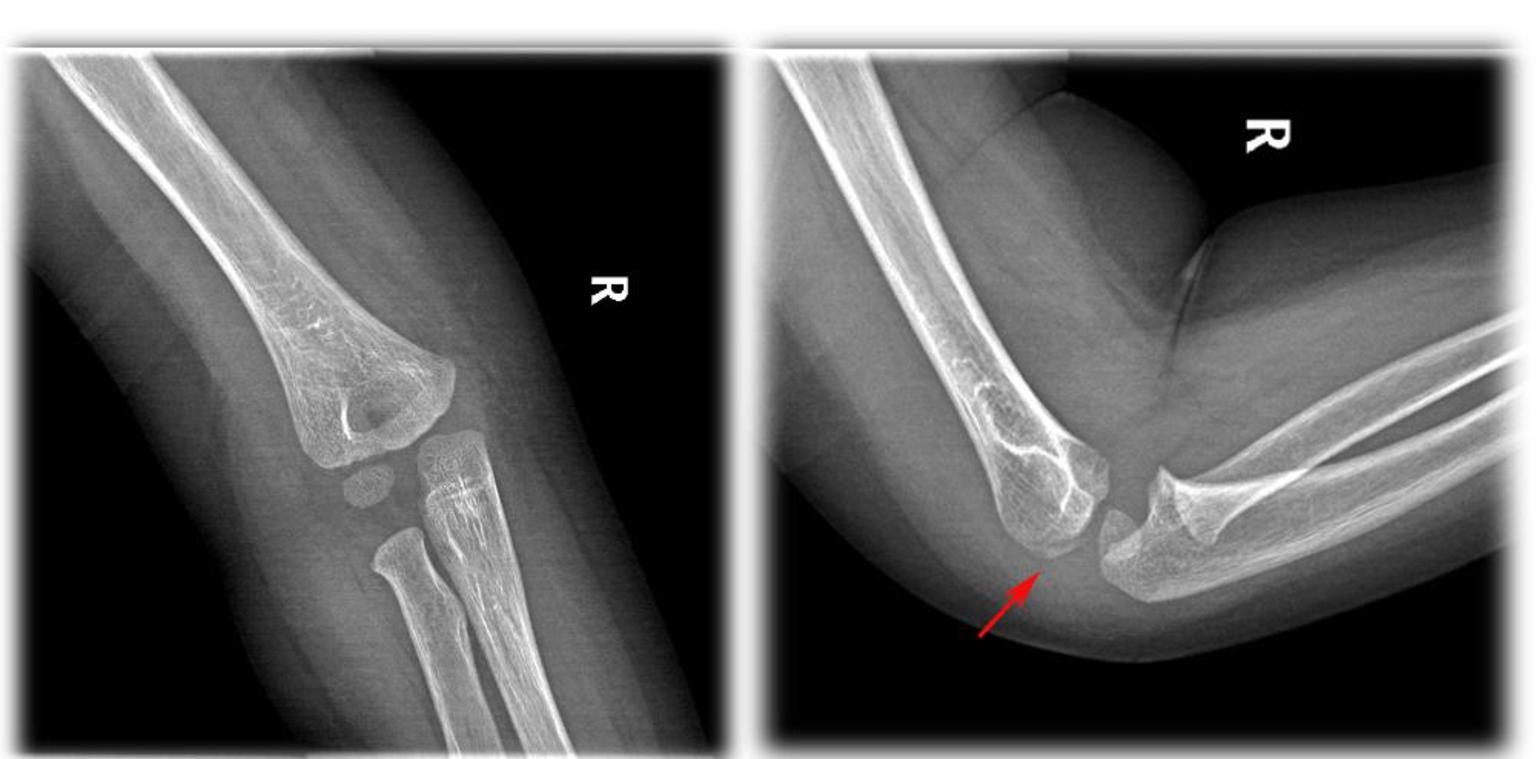

尺骨鹰嘴骨折块较小最经典治疗技术是什么 Medsci

鹰嘴骨折 肘部骨折 疾病 21

青原尺骨鹰嘴骨折合并肘关节脱位 太原长城骨伤手外科医院